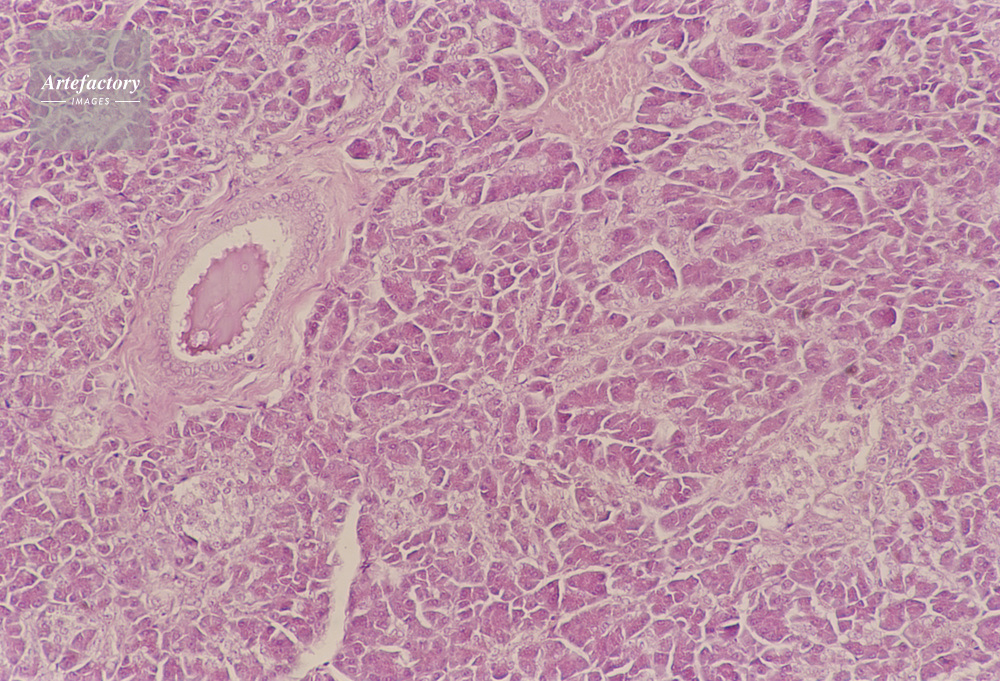

| キャプション | 膵臓,犬,10倍 | 制限事項 | ||

| ソース | ピクセル数 | 5551px × 3779px | ||

| 撮影地 | 印刷サイズ | 30.3cm × 20.6cm | ||